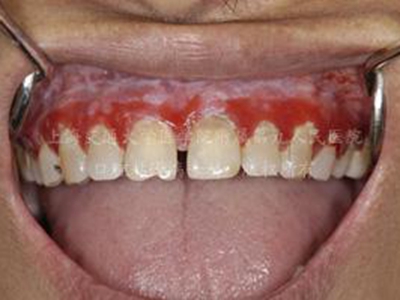

口癣一般指口腔扁平苔藓,是累及口腔,与细胞介导免疫功能紊乱有关的慢性炎症性疾病。好发于中年人,且女性多于男性,通常病程较长。患病后,临床特征为口腔黏膜损害,早期没有自觉症状,也容易被忽视,多在检查时偶然发现,其具体病因不明,通常在治疗时也需给予药物治疗及生活调理。

口癣的临床特征为口腔黏膜损害,主要为珠光白色条纹或网纹,也可为单线条或绕成环形。在舌背多为圆形或椭圆形白色斑块,损害区乳头消失而平伏。软腭或其他部位可发生透明颗粒状水疱。条纹之间的黏膜色泽可以正常或充血;有时在损害范围内某一区域发生糜烂,在唇部或颊黏膜处有时可出现针头大小、微隆的丘疹。